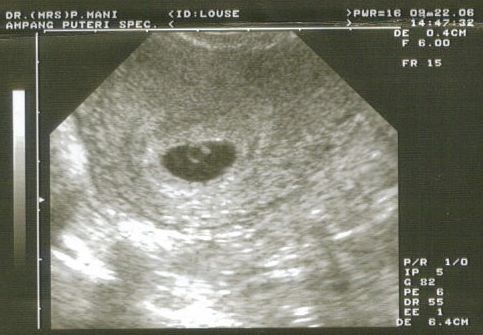

Har vedhæftet et billede, som kun er i uge 5+5..det ligner lidt mit..for ikke at sige meget..

Vedhæftede fotos (klik for at se i fuld størrelse)